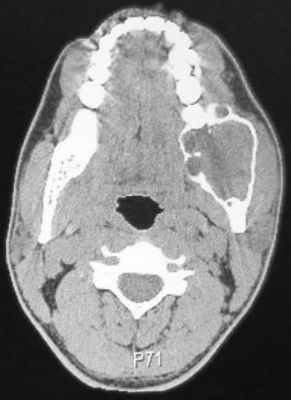

45-летний пациент обратился за помощью в отделение челюстно-лицевой хирургии с жалобами на отек в правой височной области. Припухлость не провоцировала болевых ощущений и развивалась на протяжении месяца, увеличиваясь в размерах. Признаков инфицирования в области поражения отмечено не было. В 2012 году пациент уже обращался с аналогичной проблемой в частную стоматологическую клинику. На ортопантомограмме и КТ-срезах было идентифицировано мультикистозное поражение. После биопсии стало понятно, что проблемная опухоль является амелобластомой. Пациенту была проведена процедура гемимандибулектомии. Прямо во время операции была проведена рентгенография хирургического образца опухоли для анализа состояния тканей на расстояние 1,5 см от визуализированного клинически края опухоли. Гистологический анализ подтвердил диагноз амелобластомы с атипичными признаками и мультиклеточной структурой. В 2016 году у пациента опять была отмечено припухлость в правой височной области. На МРТ было идентифицировано неоднородное усиление сигнала в данному участке размером 4,4 см × 3,7 см × 4,6 см с наличием крошечных кистозных включений (фото 4). Через доступ по скуловой кости было проведено удаление опухоли с определенным объемом окружающих тканей (фото 5-6). Сформировавшийся дефект восстановили посредством височной мышцы. После гисотоанализа хирургического образца тканей был подтверждён диагноз амелобластомы с неинвазивными краями. В данное время пациент находиться на этапе мониторинга.

Фото 4: КТ-срез, сделанный до проведения операции: визуализация рецидивирующей амелобластомы в подвисочной ямке.